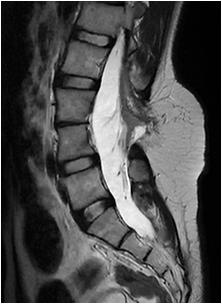

Fig 1 — CT Imaging from a patient of Basal Ganglia hemorrhage in the present study

(5) The individual regions we had observed to cause swallowing disturbance are as follows : Infarcts :

•MCA territory infarcts & PCA territory infarcts (especially of P1 and P2 region ) caused Swallowing Dysfunction.Similar findings were observed by Paciaroni M, et al17 and Javed K, et al36 respectively.

•ACA territory infarcts caused Dysphagia when associated with MCA territory infarct.

•Pontine infarct & Lateral Medullary Infarct depending on the size and subsite involved caused Swallowing Dysfunction. Similar findings were observed by Chang MC, et al21 and Ayodogdu, et al19 respectively.